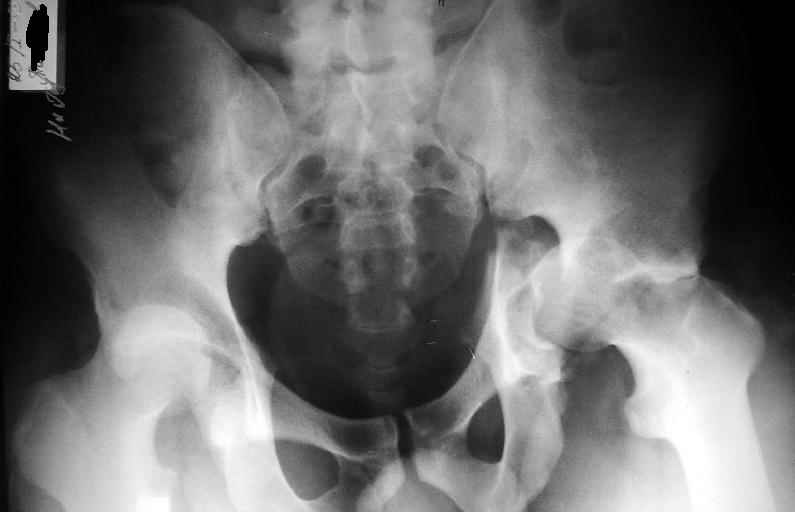

Пациент переведен в нашу клинику на 5 день после множественной травмы 25.01.2003 - двустороннее повреждение вертлужных впадин, разрыв левого крестцово-подвздошного сочленения. Вывихи обоих бедер. В месте первичного поступления подвздошный вывих правого бедра вправлен 26.01.2003, наложено вытяжение за левую вертельную область. Остеосинтез левой вертлужной впадины выполнен у нас 6.02.2003. Вопрос: надо ли синтезировать задне-верхний край правой вертлужной впадины?

правую впадину собрали здорово! Мои поздравления Рункову. Сами меня учили-учили, а где же запирательная проекция левой вертлужной

впадины. Такое впечатление что на КТ есть интерпозиция кусочком, тогда уж точно надо туда залесть, а так, я считаю не стоит.

Уважаемый Алексей, через месяц после повреждения обострять травму, чтобы продлить "колясочный" срок? Второй сустав станет опорным не скоро.Головка на Ртг концентрически вставлена, задний фрагмент не интерпонирует, лимбус,по видимому тоже, ямочный фрагмент мешать не должен,герметизирующую манжету адекватно восстановить, обычно, не удается. Выгоды от оперативного вмешательства сомнительны. Я бы оперировать не стал.Еще месяц без нагрузки (по меньшей мере) и в нашей "конторе"- МОНИКИ(Вы наверняка знаете О.Ш.Буачидзе) положились бы на ощущения пациента при активных движениях правым бедром. Можно и сейчас проверить на возможность блокады и тогда принимать окончательное решение.

Согласен, что нужна вторая проекция.

Если нагрузка на конечности будет не ранее 5-6 недель,оперировать не стоит. Считаю, что эндопротезирование справа не будет нужным.